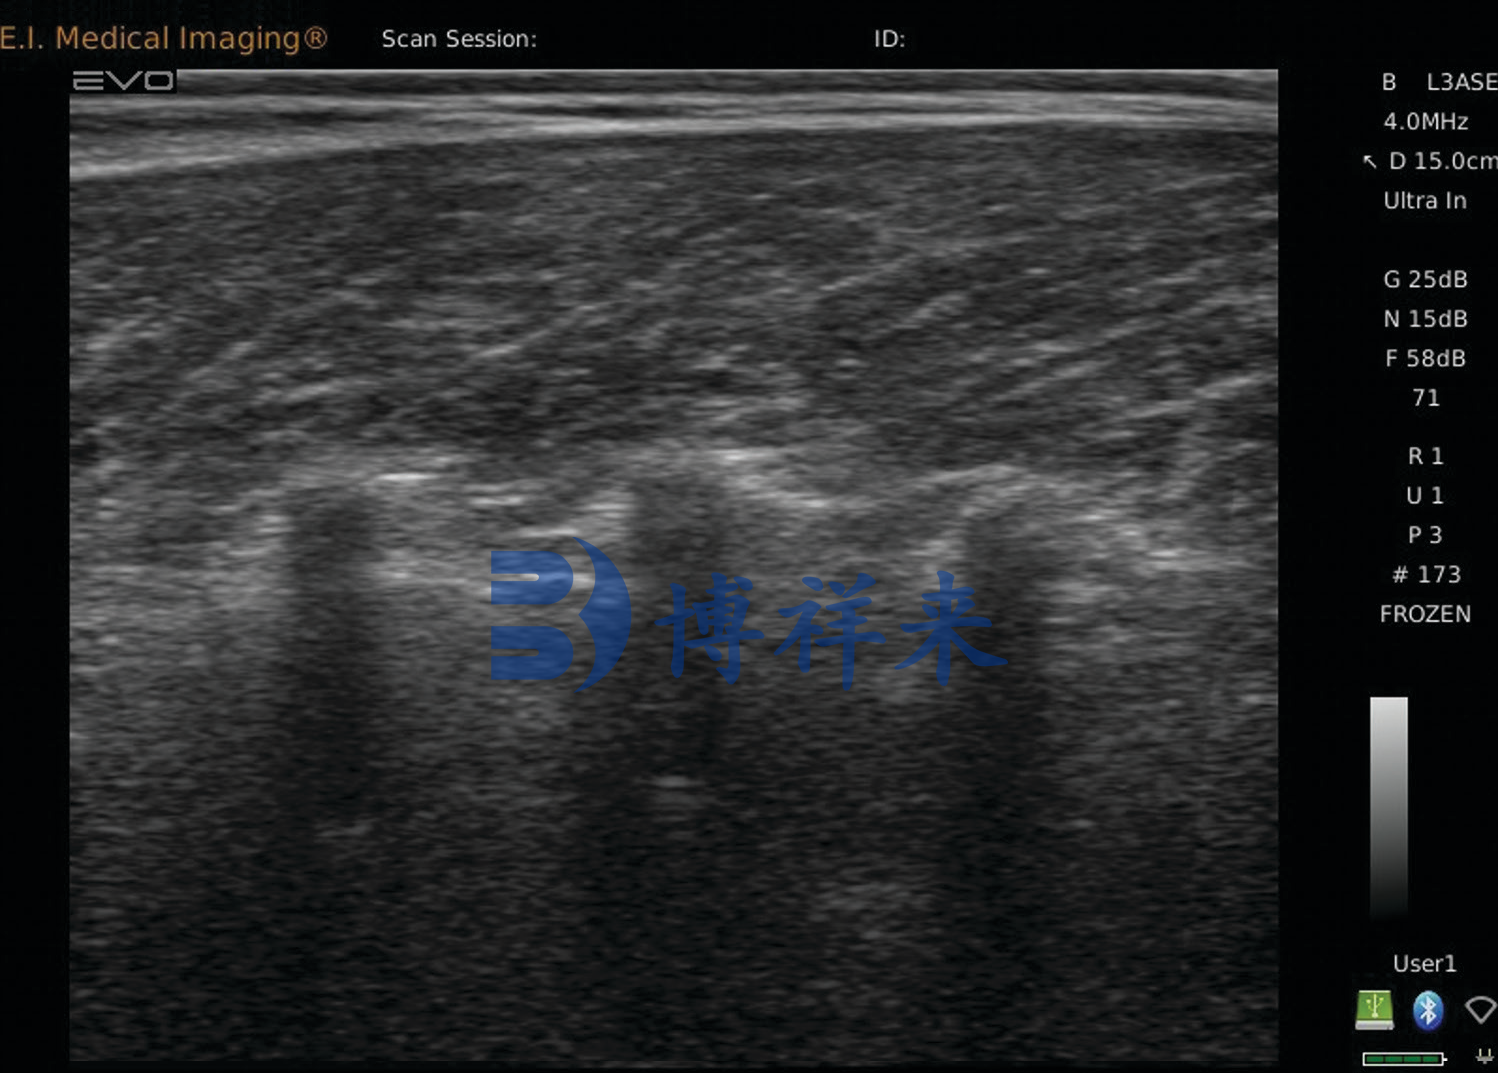

牛眼肌面积

大理石花纹(肌内脂肪,MAR)

大理石花纹(肌内脂肪)可以使用实时超声在活牛中客观地测量,并报告为肋眼肌肉中的脂肪百分比。脂肪百分比与美国农业部分级员对牛肉胴体大理石花纹的主观视觉评估相关,是胴体质量定价的主要组成部分。大理石花纹的遗传力适中。根据研究,活体动物脂肪百分比的超声预测与胴体肋眼中的实际脂肪百分比之间存在相对较高的相关性 (r = .75),尽管大理石花纹的评估准确度低于脂肪厚度和 LMA在活牛中,超声波使我们有机会客观地衡量这一经济上重要的特征。公牛的肌肉内脂肪百分比低于同等年龄、管理和遗传潜力的公牛或小母牛。研究表明,大理石花纹和脂肪厚度之间的遗传相关性非常低,这表明可以在不增加外部脂肪和相关的较低切割能力的情况下获得更高质量等级的选择。

肉牛机内脂肪超声 大理石花纹